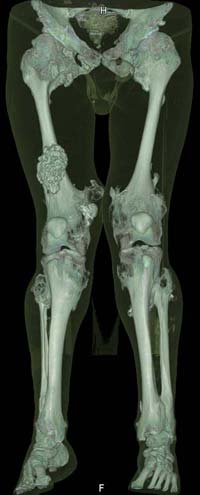

Oбратился больной 30 лет с хондродисплазией, множественными деформациями и экзостозами. Сгибательно-приводящие контрактуры Т/Б сустав, поясничный лордоз.

Интелектуально развит, работает програмистом. Болей нет. Анализы крови в пределах нормы, понижен кальций (общий Ca 1.62, N от 2.3 до 2.75;ионизорованный 0.67, N от 0.7 до 1.07) и щелочная фосфотаза -7.9. По данным КТ, оптическая плотность диафизов 150 - 200 NU (N в его возрасте 300 -350NU) метафизарный остеопороз от 100NU до отрицательных величин - 80 NU.

Планирую поэтапно, сначала справа, произвести вальгизирующе-антекурвационную остеотомию в подвертельной области бедра, соответственно варизирующую на голени, фиксация фрагментов спице - стержневым аппаратом Илизарова. Одновременно удалить большой экзостоз в области конен. сустава

30 years old male with chondrodysplasia and multiple exostoses admitted.Multilevel deformities, flexion-adduction limitation of hip ROM, lumbar lordosis. Intellectually developed, working in some software company. Painless. Blood tests are normal, except low Calcium (total serum Ca 1. 62, N is 2.3 - 2.75; ionized 0.67 N is 0.7 -1.07) and low alkaline phosphatase 7.9. Diaphysis bone density is about 150 - 200 NU (N in his age is 300 - 350NU). Metaphis osteoporosis is from 100NU to minus 80 NU.

Patient has strong motivation to treatment. He wants to deformities be corrected and few exostoses in knee areas be removed.

I am thinking about subtrochanteric valgization osteotomy of femur, varization osteotomy of tibia, fixation with Ilizarov - hybrid type external fixator, simultaneously removal of big exostosis in right knee area. But, before do something, I would like to know your valuable opinions. Myquestions are:

The x-ray is satisfactory for analysis. In The AP view, The knee and ankle should be exactly anterior and the patella should be facing forward, then we can measure the deformity in the AP. Another lateral view of the whole lower limb should be taken, so we can correct 6 dimensions (X, Y and Z axes and Alpha, Beta and Gamma rotation).

But it seemes to me that he has distal femoral valgus and may be also distal tibial. But anyway, we have to measure a good x-ray (lateral distal femoral angle, Medial proximal tibial angle and also the distal tibial angles).

After Dr Elbatrawy saw the CT scans he added - the case has multible exostosis and the ulna also may need lengthening on both sides; he will need follow up, as one of the multible exostosis may transform to Chondrosarcoma on top of its cartilagenous cap. It is a common problem associated with this condition.